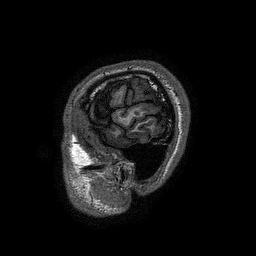

Encefalo: immagini sagittali pesate in T1

Immagine 1/13

Selezione di immagini pesate T1 ad alta risoluzione spaziale (dimensione del voxel 1x1x1 mm)